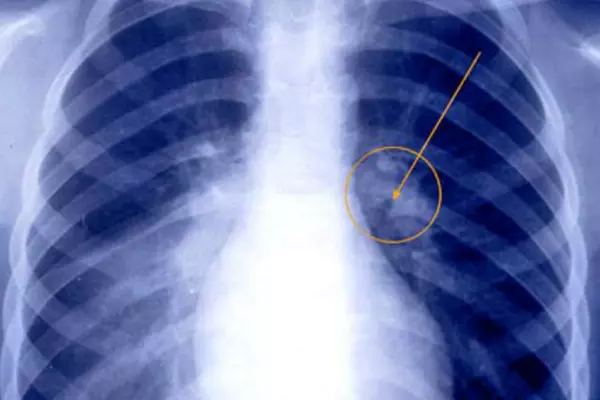

Самостоятельно по визуальным признакам определить вид пневмонии, бронхита, гриппа, туберкулеза невозможно, необходимо пройти рентген обследование. Характерные особенности легочных заболеваний:

— на рентгенограмме грудной клетки, в области легких видно затемнение, как на фото ниже:

- рентгенография легких;

Бронхит

От других лёгочных патологий бронхиты отличаются в первую очередь областью локализации воспалительного процесса. При этом заболевании поражается слизистая оболочка бронхов, тогда как у больного пневмонией затрагиваются альвеолярные участки лёгких. На рентгене очаги бронхита чаще всего визуализируются слабо.